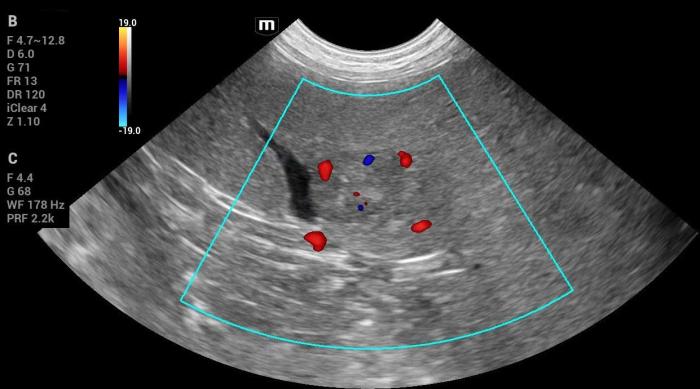

- Vascularización Doppler color positiva (Figura 18-19).

Hallazgos elastográficos (Natural Touch Elastography®): la lesión de mayor tamaño mostró rigidez elevada, significativamente superior al parénquima esplénico normal (Figura21-22).

Este comportamiento coincide con el patrón elastográfico típico de lesiones malignas descrito en la literatura5, donde los tumores esplénicos (incluyendo hemangiosarcoma) tienden a presentar velocidades de onda de corte superiores a las de lesiones benignas.

Las mediciones fueron técnicamente consistentes, sin artefactos respiratorios ni subcapsulares.

Diagnóstico histopatológico: el espécimen esplénico obtenido mediante esplenectomía confirmó hemangiosarcoma.

Interpretación: la combinación de esplenomegalia severa, masa sólida de ecogenicidad mixta, vascularización positiva y rigidez marcadamente aumentada en la elastografía constituye un patrón fuertemente sugestivo de malignidad. Este conjunto de hallazgos es coherente con lo reportado para tumores esplénicos de origen mesenquimal, incluida su variante más frecuente en el perro: el hemangiosarcoma.